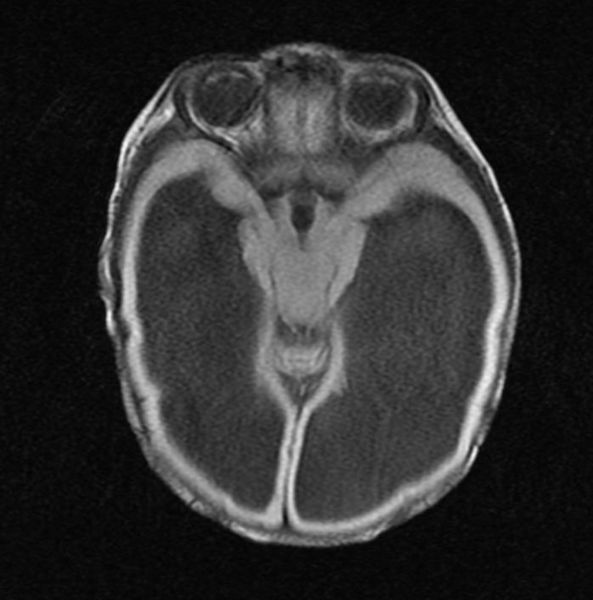

Hydrocephalus MRI – wikidoc

MRI of hydrocephalus – Stock Image – M170/0370 – Science Photo Library

Severe hydrocephalus | Image | Radiopaedia.org

Severe hydrocephalus | Radiology Case | Radiopaedia.org

Hydrocephalus MRI – wikidoc